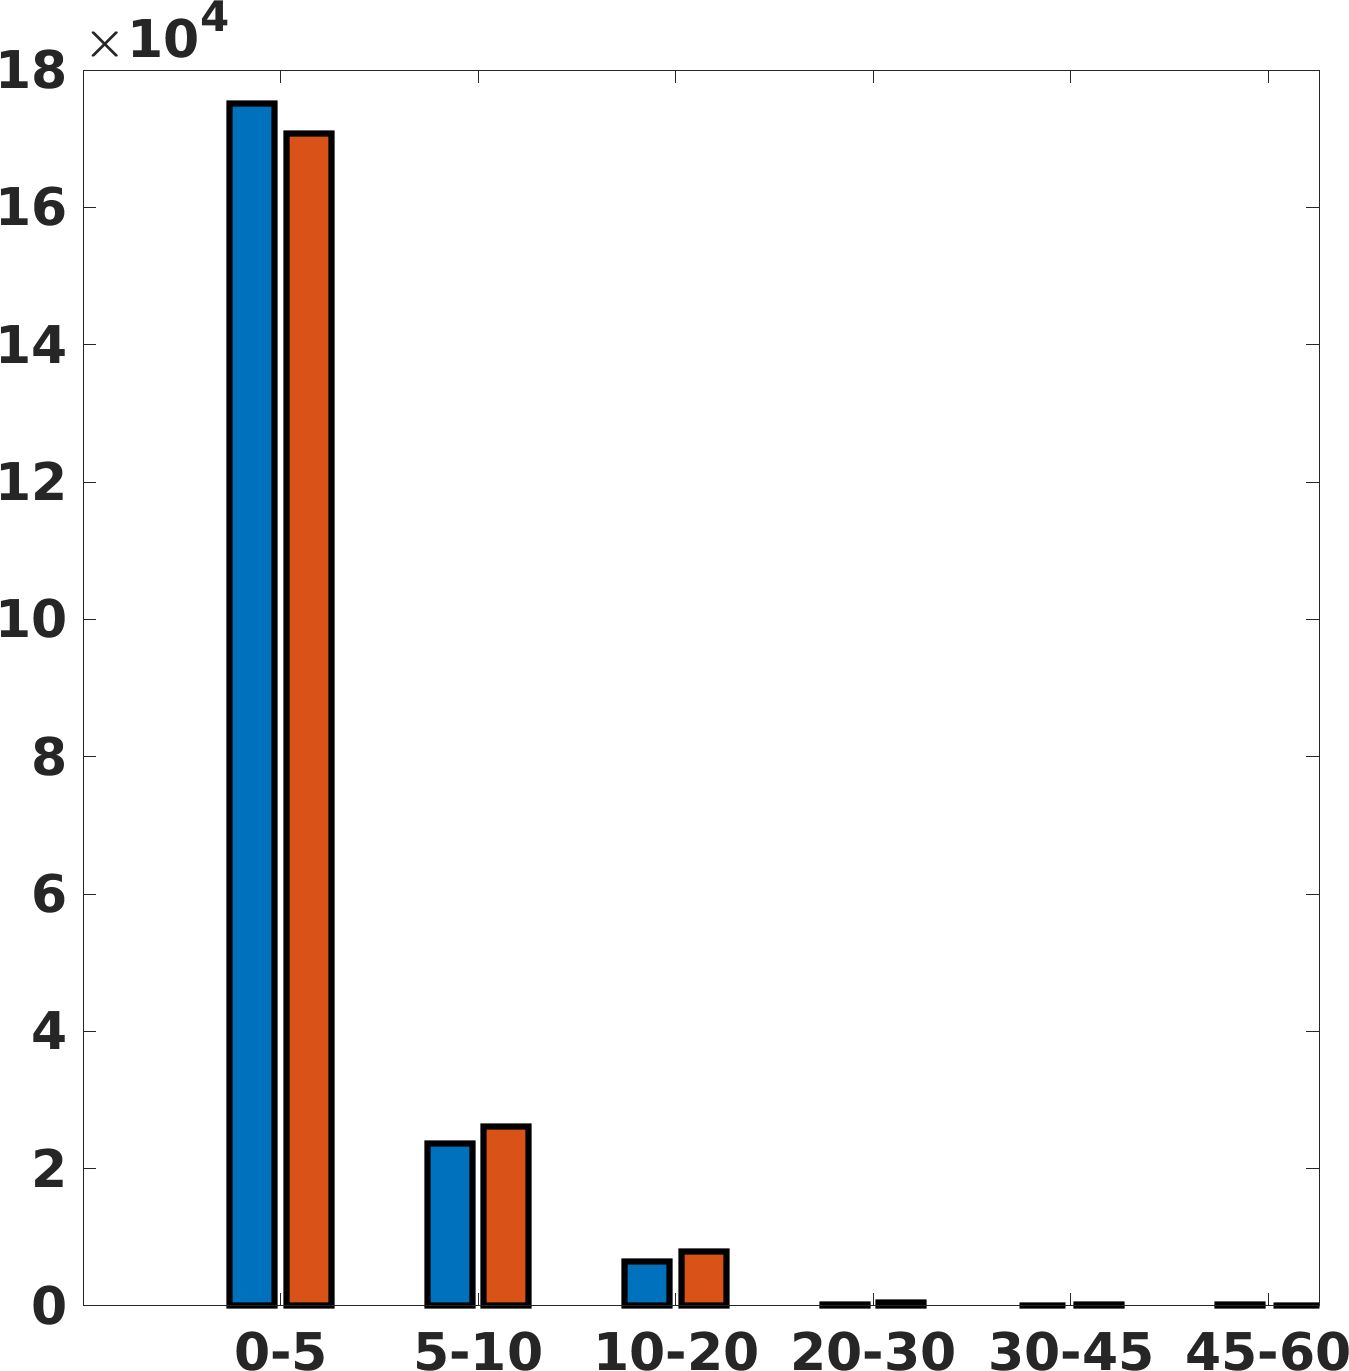

Fig. 7(a-b-c, right) shows the histogram of the absolute value of the error with respect to the target image, of the prediction and Cubic convolution results, respectively. The histograms show the number of pixels where the prediction error is lower than 5 (i.e., the first bin of the histogram), which means very similar to the target when visually analysing the images. From the Cubic convolution to the predicted images, this value increases of on obstetric 4X raw images, on cardiac 4X raw images, and on abdominal 4X raw images.

Fig. 8 shows the box plot of the SSIM (a-b-c, left) and MAE (a-b-c, right) quantitative metrics, as performed for PSNR metric. Also, these metrics show that our method improves the results of Cubic convolution both in terms of average value and variability. For example, the SSIM median value improves of on obstetric 4X images and the MAE median value improves of on cardiac 2X images.

Fig. 17 (right) shows the histogram of the absolute value of the error with respect to the target, of the prediction and Cubic convolution respectively. This result shows that our framework increase of and (2X and 4X, respectively) the number of pixels where the prediction error is lower than 5, which is very similar to the target when visually analysing the images, and improved with respect to the learning framework applied to raw images. According to Fig. 18, our method improves the accuracy of Cubic convolution. For example, the SSIM increases of on cardiac 2X and the MAE increases of on abdominal 4X.